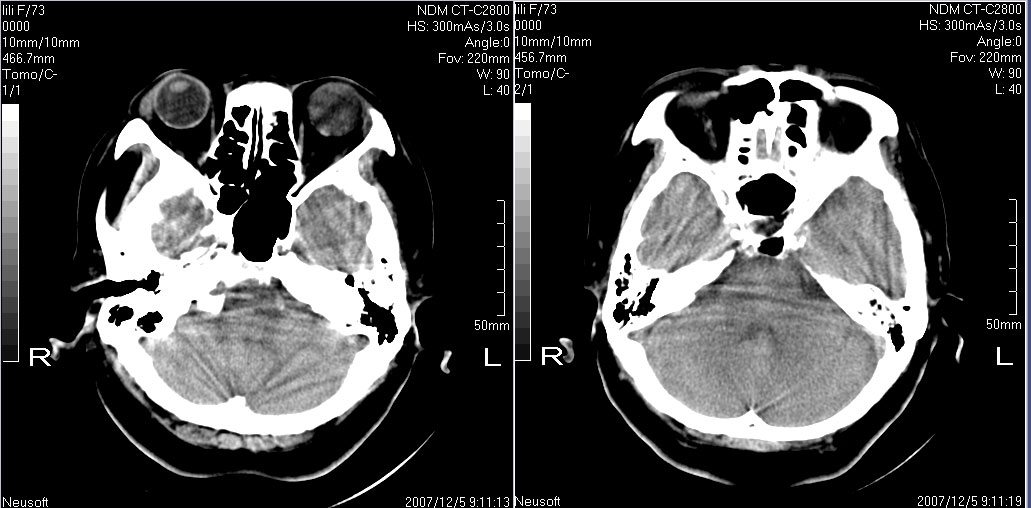

标题: CT10819:女,72,有高血压病史,突然寡言少语3日. [打印本页]

女,72,有高血压病史,突然寡言少语3日.

双侧基底节、胼胝体膝部多发腔隙性脑梗塞。

双侧基底节、左侧额叶 胼胝体膝部多发腔隙性脑梗塞。